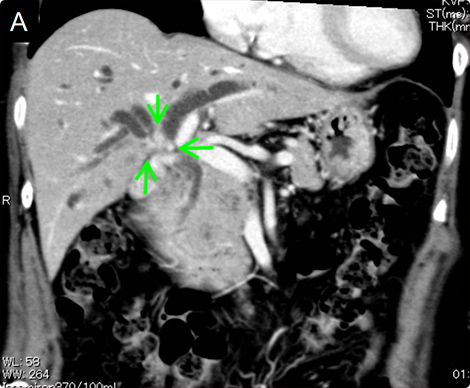

図6 門脈塞栓術後に拡大右肝切除を行った肝門部胆管癌-1

A.入院時造影CTで右胆管優位の肝門部胆管癌を認めました(矢印)。

B.C.左胆管のドレナージのみでは減黄できなかったため、3本の内視鏡的胆管ドレナージ(ERBD)を挿入しました(矢印)。

• 78歳、女性、総ビリルビン 11.4 mg/dl